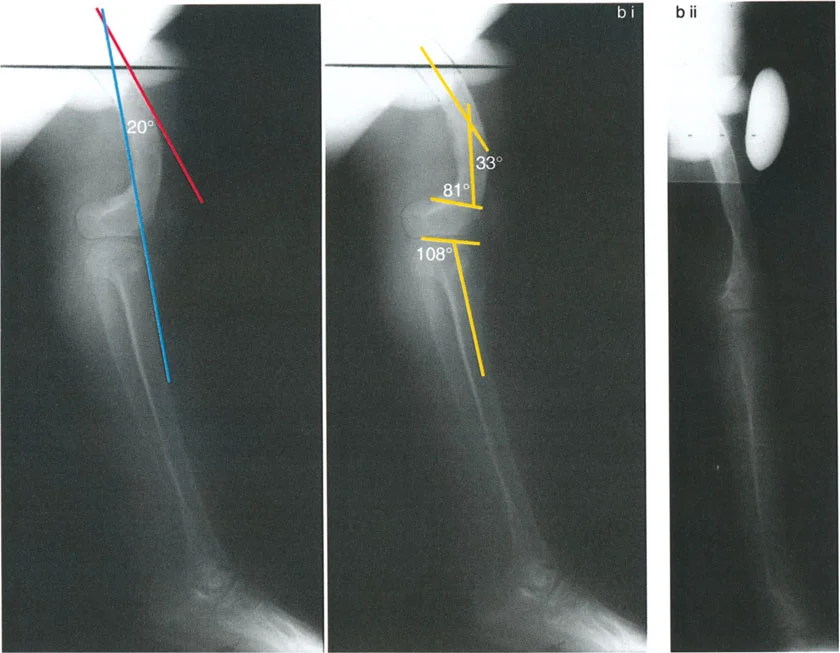

تُعد الأشعة التصويرية ضرورية لتأكيد التشخيص وتحديد مدى الضرر وموقع التشوهات العظمية بدقة:

- الأشعة السينية (X-rays):

- الأشعة الأمامية الخلفية (AP View) والجانبية (Lateral View): تُظهر حالة العظام، تآكل الغضروف (يُلاحظ كضيق في المسافة المفصلية)، وجود نتوءات عظمية (Osteophytes)، وأي تشوهات عظمية واضحة.

- الأشعة السينية الطويلة للطرف السفلي بالكامل أثناء الوقوف (Standing Long-Leg AP View): تُعد هذه الأشعة حاسمة لتقييم المحاذاة الميكانيكية للطرف السفلي بأكمله. تُظهر بدقة درجة الانحراف الأفحج (Varus) أو الأروح (Valgus) وتساعد في تحديد مركز دوران التشوه (CORA).

- الأشعة الجانبية الطويلة للطرف السفلي بالكامل أثناء الوقوف في أقصى بسط (Standing Long-Leg Lateral View in Maximum Extension): تُستخدم لتقييم تحدد حركة الركبة (FFD) والركبة الارتدادية (Recurvatum)، وتحديد ما إذا كان التشوه عظميًا أو ناتجًا عن تقلص في الأنسجة الرخوة.

تصحيح الركبة الارتدادية (Recurvatum Deformity - Hyperextension)

الركبة الارتدادية هي فرط البسط في الركبة. غالبًا ما تكون غير مصحوبة بأعراض في الأشخاص ذوي العضلات السليمة، ولكنها قد تسبب مشاكل في حالات ضعف العضلات أو التشوهات العظمية.

- التشخيص: يجب تحديد ما إذا كانت الارتدادية عظمية (تقوس خلفي في الفخذ أو الساق) أو ناتجة عن رخاوة في الأنسجة الرخوة أو ضعف عضلي.

- قطع العظم الانثنائي (Flexion Osteotomy):

- إذا كان التشوه عظميًا (تقوس خلفي)، يتم إجراء قطع عظم انثنائي في عظم الفخذ أو الساق لتصحيح الارتدادية.

- الأستاذ الدكتور محمد هطيف يشدد على أهمية عدم استخدام قطع عظم الفخذ الانثنائي لتصحيح ارتدادية الساق، والعكس صحيح، لتجنب الانزلاق الخلفي أو الأمامي للركبة.

- اعتبارات خاصة: في المرضى الذين يعانون من ضعف عضلي (مثل شلل الأطفال)، قد يحتاج التصحيح إلى فرط تصحيح بسيط (overcorrection) إلى وضعية انثناء لضمان ثبات الركبة ومنع فرط البسط غير المتحكم فيه.